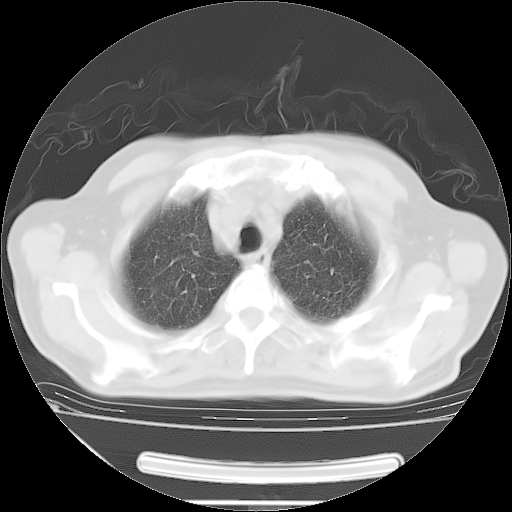

今天复查肺部CT,发现双肺广泛磨玻璃样改变。所以我把3月19日和5月9日相隔50天的肺部CT上传。请大家会诊。

2009年3月19日肺部CT片。

5月9日肺部CT(在4月27日齐鲁医院肺部CT描述部分肺组织磨玻璃样改变,12天后肺组织广泛磨玻璃样改变)